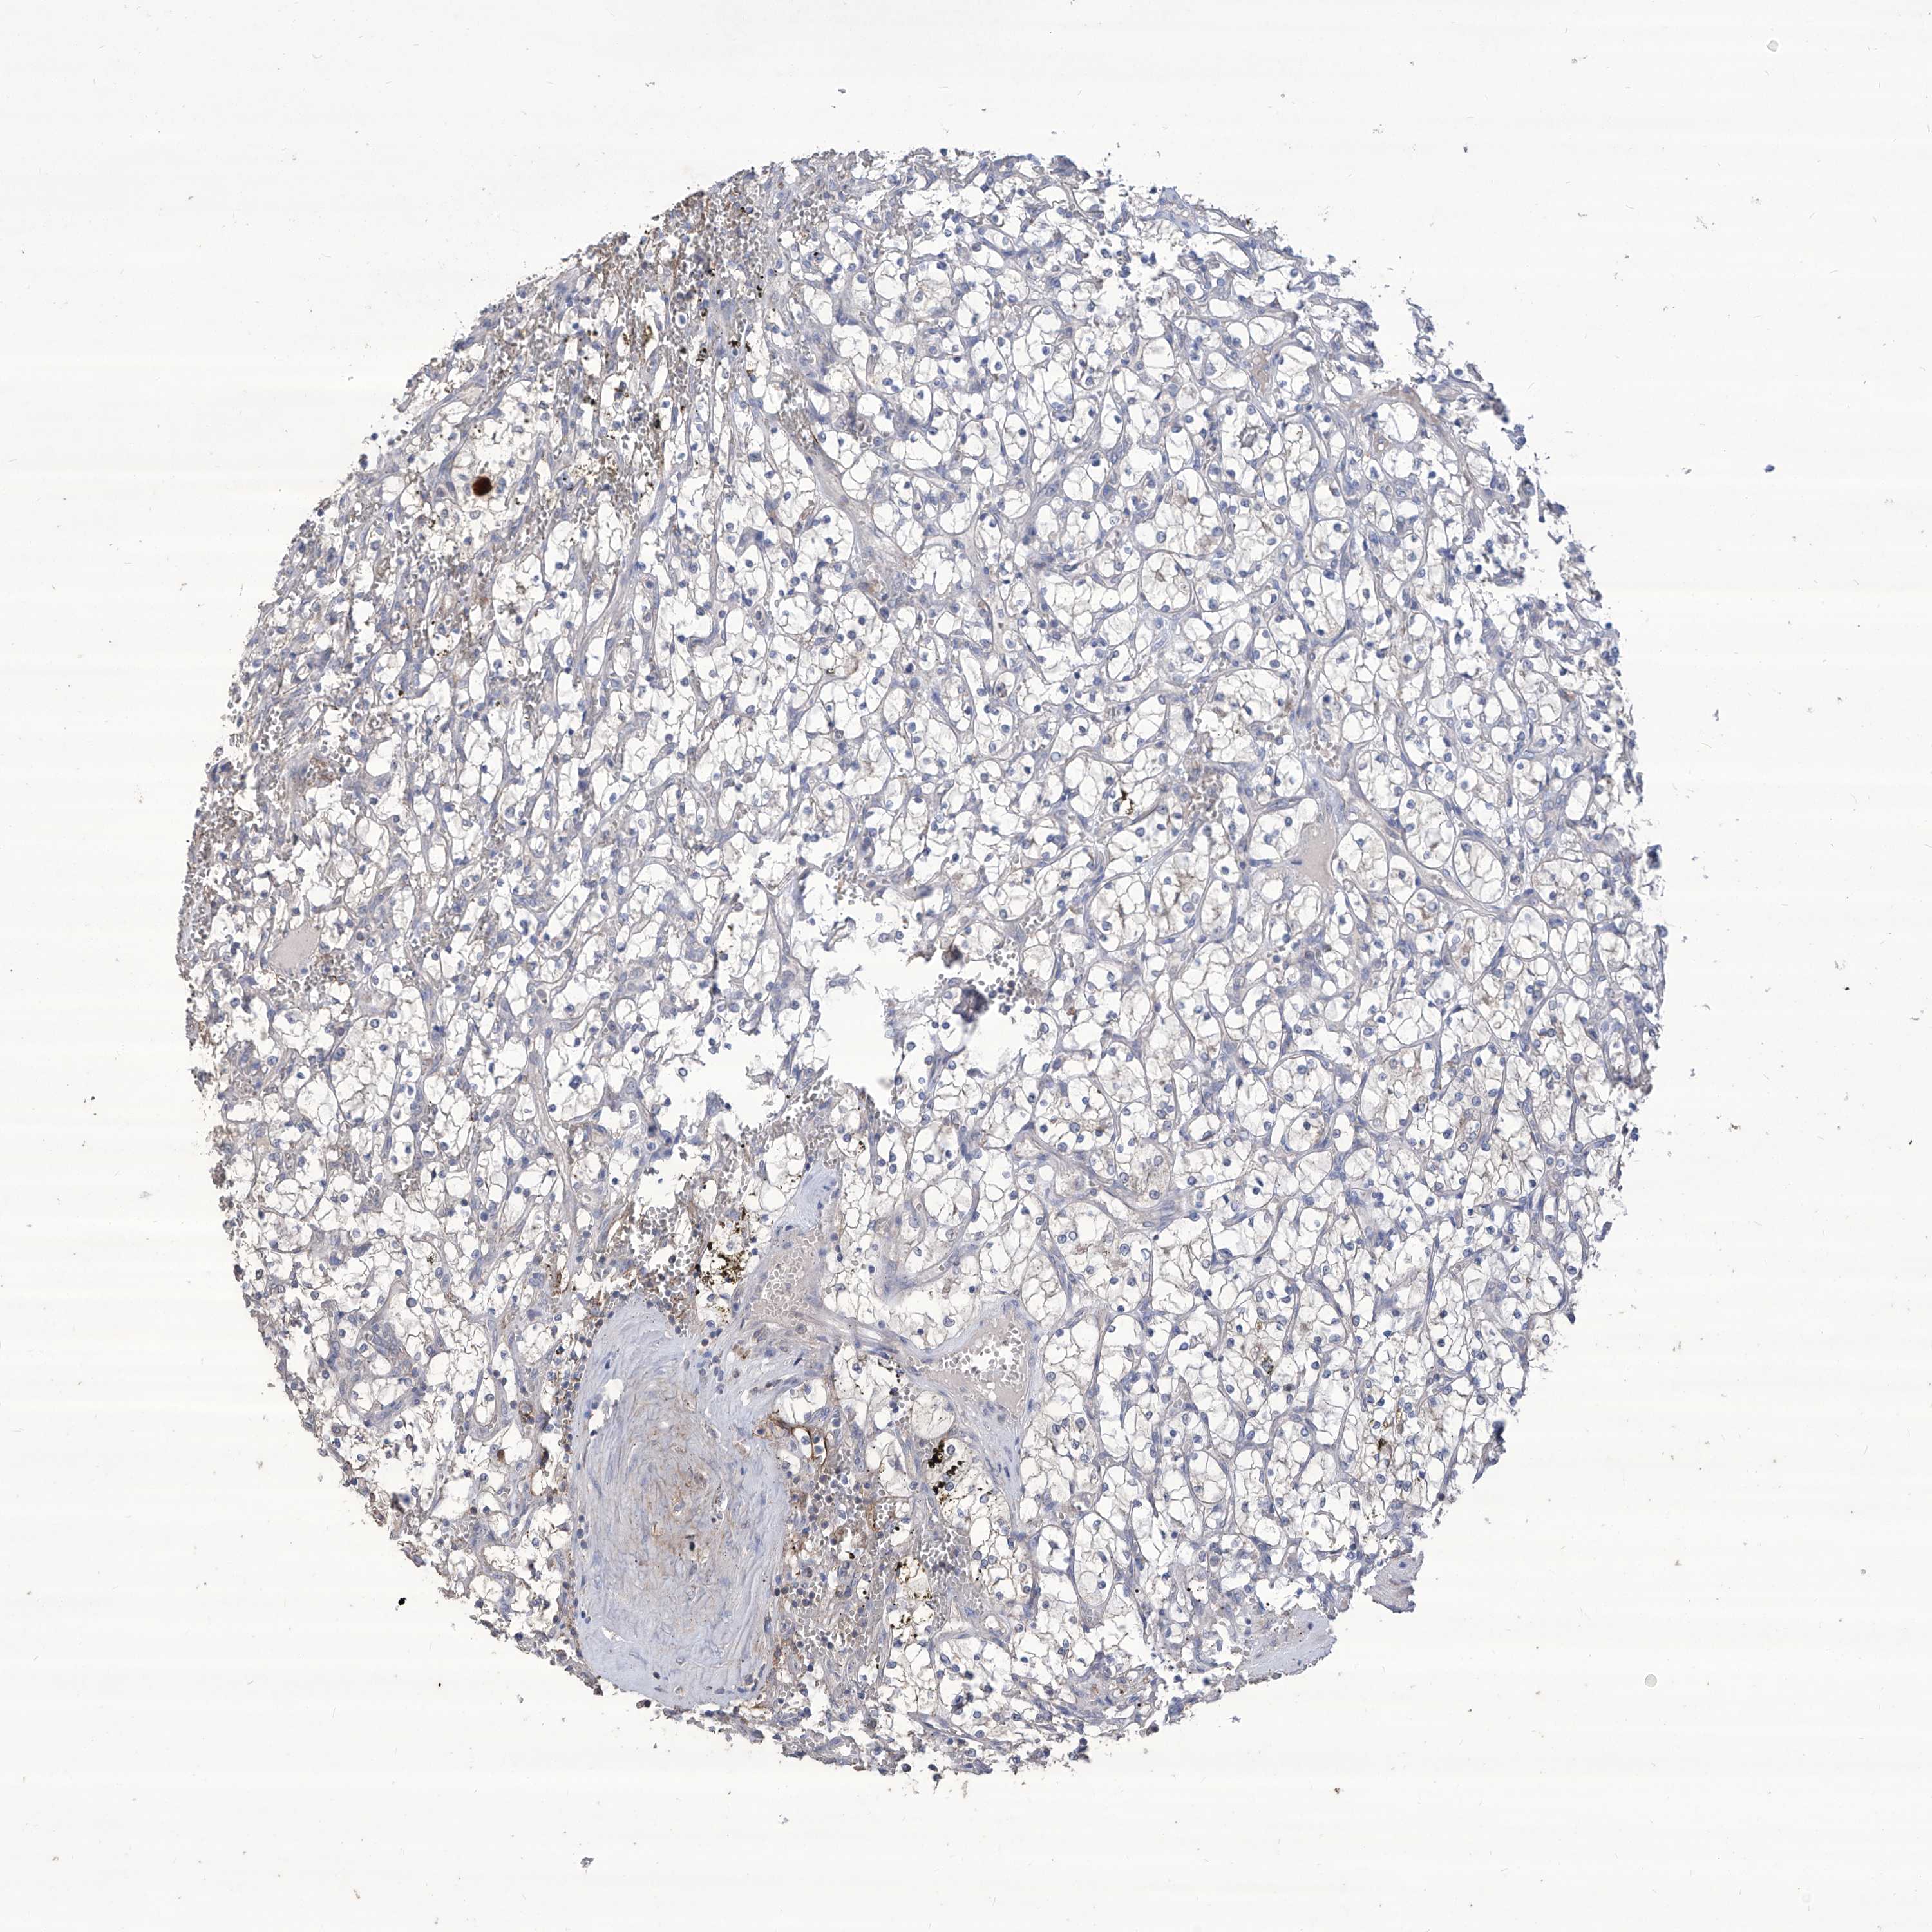

KIDNEY RENAL CLEAR CELL CARCINOMA (VALIDATION) - Interactive survival scatter ploti

The Survival Scatter plot shows the clinical status (i.e. dead or alive) for all individuals in the patient cohort, based on the same data that underlies the corresponding Kaplan-Meier plots. Patients that are alive at last time for follow-up are shown in blue and patients who have died during the study are shown in red.

The x-axis shows the expression levels (FPKM) of the investigated gene in the tumor tissue at the time of diagnosis. The y-axis shows the follow-up time after diagnosis (years). Both axes are complimented with kernel density curves demonstrating the data density over the axes. The top density plot shows the expression levels (FPKM) distribution among dead (red) and alive patients (blue). The right density plot shows the data density of the survived years of dead patients with high and low expression levels respectively, stratified using the cutoff indicated by the vertical dashed line through the Survival Scatter plot. This cutoff is automatically defined based on the FPKM cutoff that minimizes the p-score. The cutoff can be changed by dragging the vertical line or by entering a cutoff value in the square labeled "Current cut-off".

Under the Survival Scatter plot the p-score landscape (black curve; left axis) is shown together with dead median separation (red curve; right axis). Dead median separation is the difference in median mRNA expression between patients who have died with high and low expression, respectively. It is calculated as follows: median FPKM expression of dead patients with high expression - median FPKM expression of dead patients with low expression. This is intended to aid the user in visually exploring custom cutoffs and the associated p-scores and dead median separation.

Individual patient data is displayed and can be filtered by clicking on one or more of the category buttons on the top of the page. Categories describing expression level and patient information include: high, low, alive, dead, female, male and tumor stages. The scale of the x-axis can be toggled between linear and log-scale by clicking on the "x log" button. Mouse-over function shows TCGA ID, patient information and mRNA expression (FPKM) for each patient.

& Survival analysisi

Kaplan-Meier plots summarize results from analysis of correlation between mRNA expression level and patient survival. Patients were divided based on level of expression into one of the two groups "low" (under cut off) or "high" (over cut off). X-axis shows time for survival (years) and y-axis shows the probability of survival, where 1.0 corresponds to 100 percent.

TXNIP is not prognostic in Kidney Renal Clear Cell Carcinoma (validation)

Best expression cut offi

Based on the FPKM value of each gene, patients were classified into two groups and association between prognosis (survival) and gene expression (FPKM) was examined. The best expression cut-off refers the FPKM value that yields maximal difference with regard to survival between the two groups at the lowest log-rank P-value. Best expression cut-off was selected based on survival analysis .

When clicking on this number, the vertical dashed line indicating cut-off, the interactive survival plot, and the Kaplan-Meier curve will be adjusted to show results based on the best expression cut-off.

: 478.37

P scorei

Log-rank P value for Kaplan-Meier plot showing results from analysis of correlation between mRNA expression level and patient survival.

N/A

Average pTPM 691.0

Number of samples 100